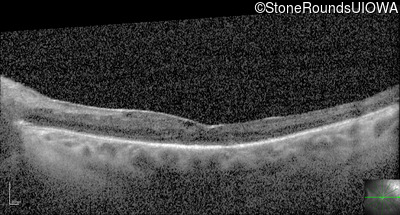

Optical Coherence Tomography - Right - 20/125

Exemplar / OCT Stack

OCT Stack